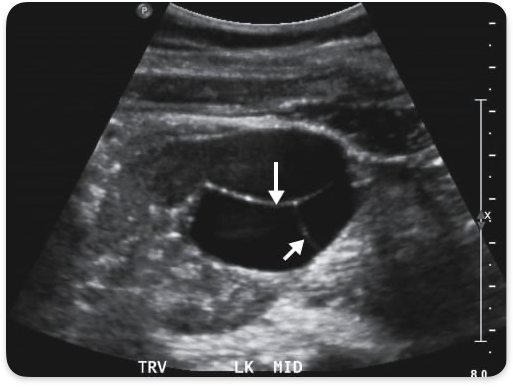

Adpkd , autosomal dominant polycystic kidney disease. Bilateral enlarged kidneys, cysts in other organs.